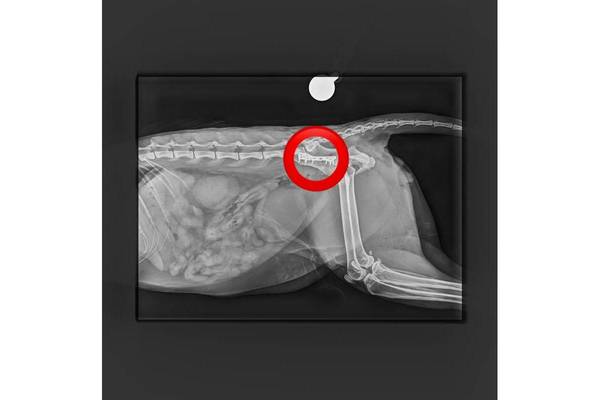

Kürzlich hat der Tierschutzhof Pfotenhilfe einen schwer verletzten Kater aufgenommen, der in Mondsee (OÖ) gefunden wurde und ihn unverzüglich zum auf orthopädische Chirurgie spezialisierten Tierarzt Mag. Daniel Eschlböck in Alkoven (OÖ) gebracht. Dieser hat auf den Röntgenbildern multiple Beckenbrüche festgestellt und bereits eine Seite operiert, jetzt folgt die zweite Operation. Die Verletzungen deuten auf einen Autounfall oder Sturz hin. Der Kater ist natürlich stationär bei ihm untergebracht.